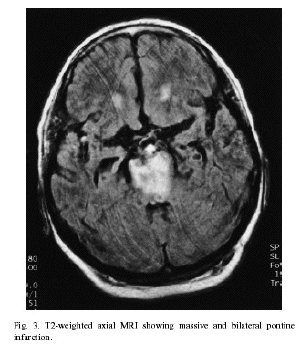

สภาพสมองของผู้ป่วย โรค Locked-in syndrome